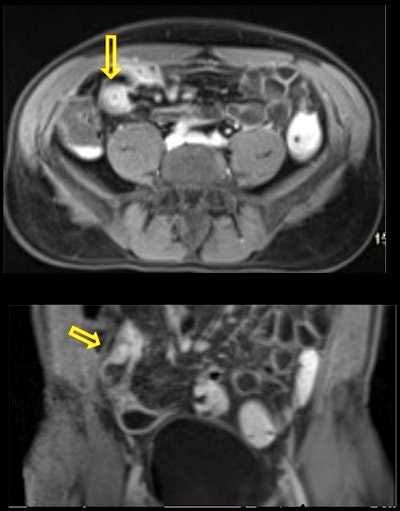

In their analysis, they identified the following genitourinary incidental findings:

- Inguinal hernia: An inguinal hernia occurs when the intestines or fat from the abdomen bulge through the lower abdominal wall into the inguinal, or groin, area.

- Diverticular disease: Diverticulosis is the condition of having multiple pouches (diverticula) in the colon that are not inflamed. These are outpockets of the colonic mucosa and submucosa through weaknesses of muscle layers in the colon.